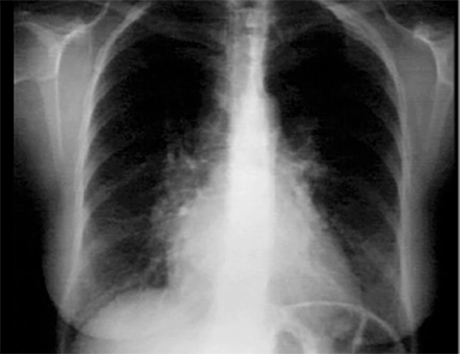

These chest X rays show right ventricular enlargement and left atrial enlargement. The PA view demonstrates left atrial enlargement reflected by the

double contour within the heart border,

an elevated

left mainstem bronchus

and an enlarged

left atrial appendage

causing straightening of the left heard border. Note also that the

cardiothoracic ratio

is greater than 50%, reflecting cardiomegaly. In the lateral view,

left atrial enlargement

is further reflected by the prominent posterior left atrial shadow. Right ventricular enlargement is best seen in this view and is manifested by

obliteration of the retrosternal air space.